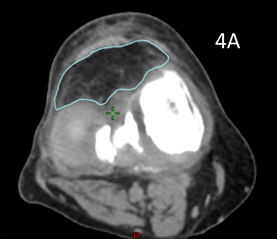

For RT planning, the RO marked on skin the radiation field edges of the volume to be treated. These marks could be upper, lower, medial and lateral and any other limits. These were in general aimed to cover all the synovium associated with that joint volume. (Figure 1) These marks were interpreted by the planning radiation therapists (RThers) to be one centimetre (cm) outside limits of the proposed clinical target volume (CTV) and eight millimeters (mm) outside of the planning target volume (PTV).14 (Figure 1A)

These volumes were then approved by the RO. The target volume was intended to be the joint including synovium with prescription to cover the PTV with 95% of the prescription dose. (Figure 2)

Figure 2 Contouring and dosimetry.

Figure 2A Axial planning CT slice through zero plane of knee in Figure 1A showing PTV (blue volume indicated by white arrow) as 2 mm expansion of CTV which was an auto contour of the bone.

Figure 2B Axial planning CT slice through zero plane showing dosimetry as colour wash set at 2.5Gy level. Notice excellent conformity to PTV and homogeneity within the PTV and sparing of soft tissues that may not have been spared by a 3DCRT approach.